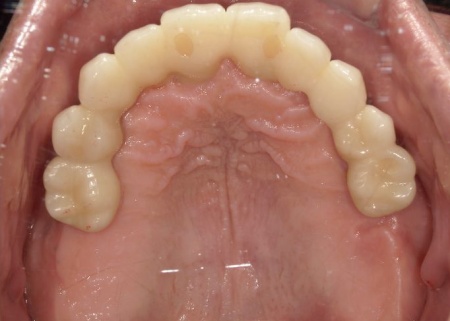

①上の歯7本、右下の奥歯2本を抜歯する。上あごには抜歯と同時に4本のインプラントを埋め、その上に10本分の仮歯を取り付けるオールオンフォーを行う。

インプラントの種類には、あごの骨と結合する力に優れたオステム社のETⅢを採用。インプラントが骨にしっかり定着するまでの間は、通常のインプラントよりも細い暫間インプラントを一時的に併用して仮歯を支える

②インプラントが安定したことを確認してから、仮歯を外して最終的な人工歯を装着する

最後に、残っている下の歯としっかりと噛み合っていることを確認し、治療を終了しました。